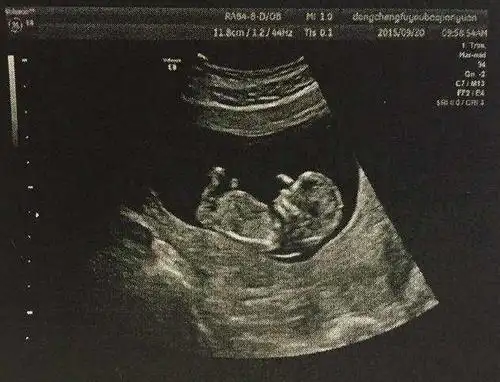

生儿子的四维彩超图片揭秘,三个亮点未必怀男孩

nt三个亮点是男孩女孩